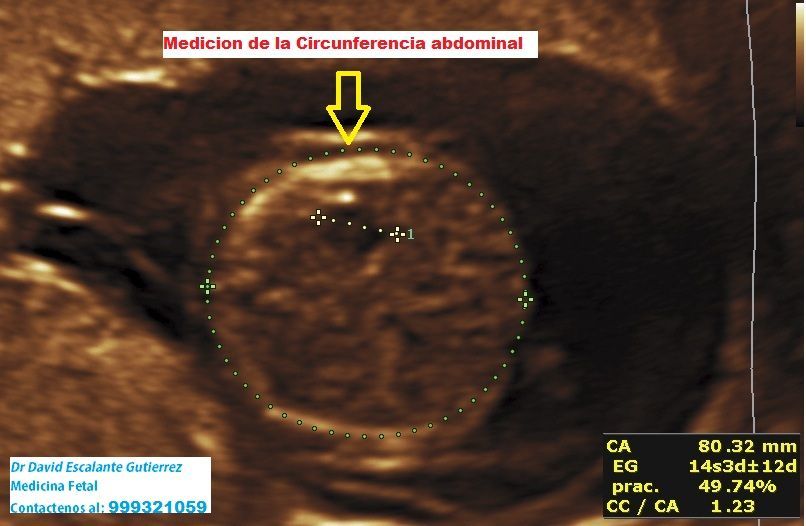

Realizamos las ecografías de viabilidad del embarazo, genética, morfológica, de bienestar fetal, ecocardiografías fetales, así como procedimientos invasivos como biopsia de vellosidades coriales y amniocentesis.